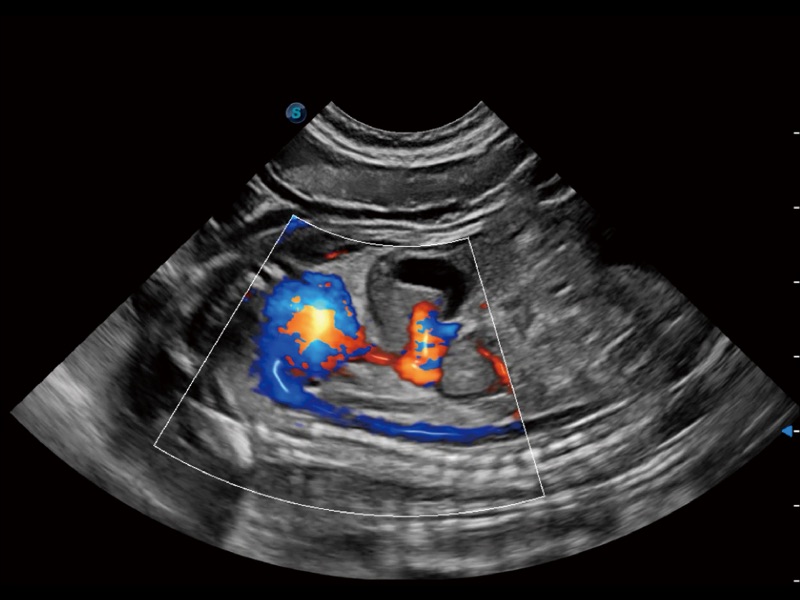

(犬)胎儿主动脉弓立体血流

(犬)四腔心